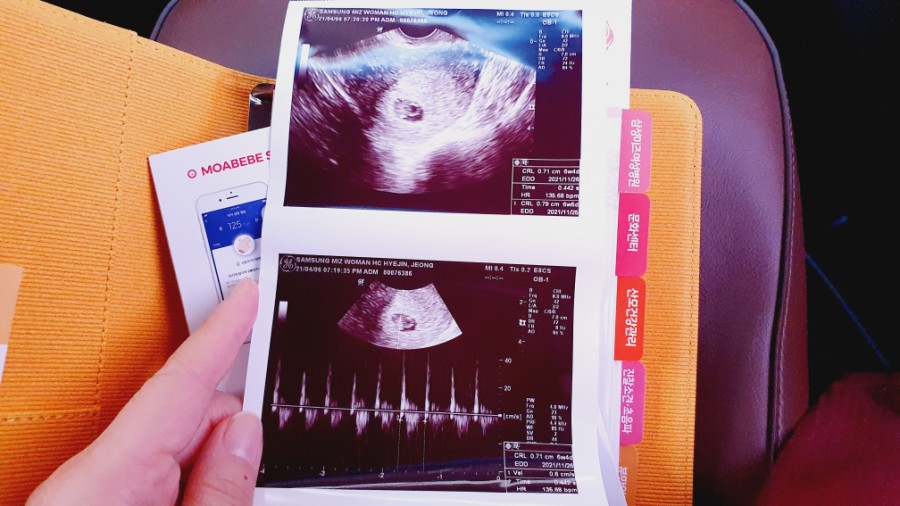

임신 6주차 아기의 심장 소리를 듣고 신기하고 감동적인 기쁨에 젖었다.그냥 신기해. 심장 소리를 내도 아직 내 안에 아기가 있다는 실감이 안 나.나중에 얘가 동그랗게 클 거라고 생각하니까 그것도 신기하다

심장 소리를 듣고 산전 검사를 했다.

심음을 듣고 모자수첩을 받아 들었다